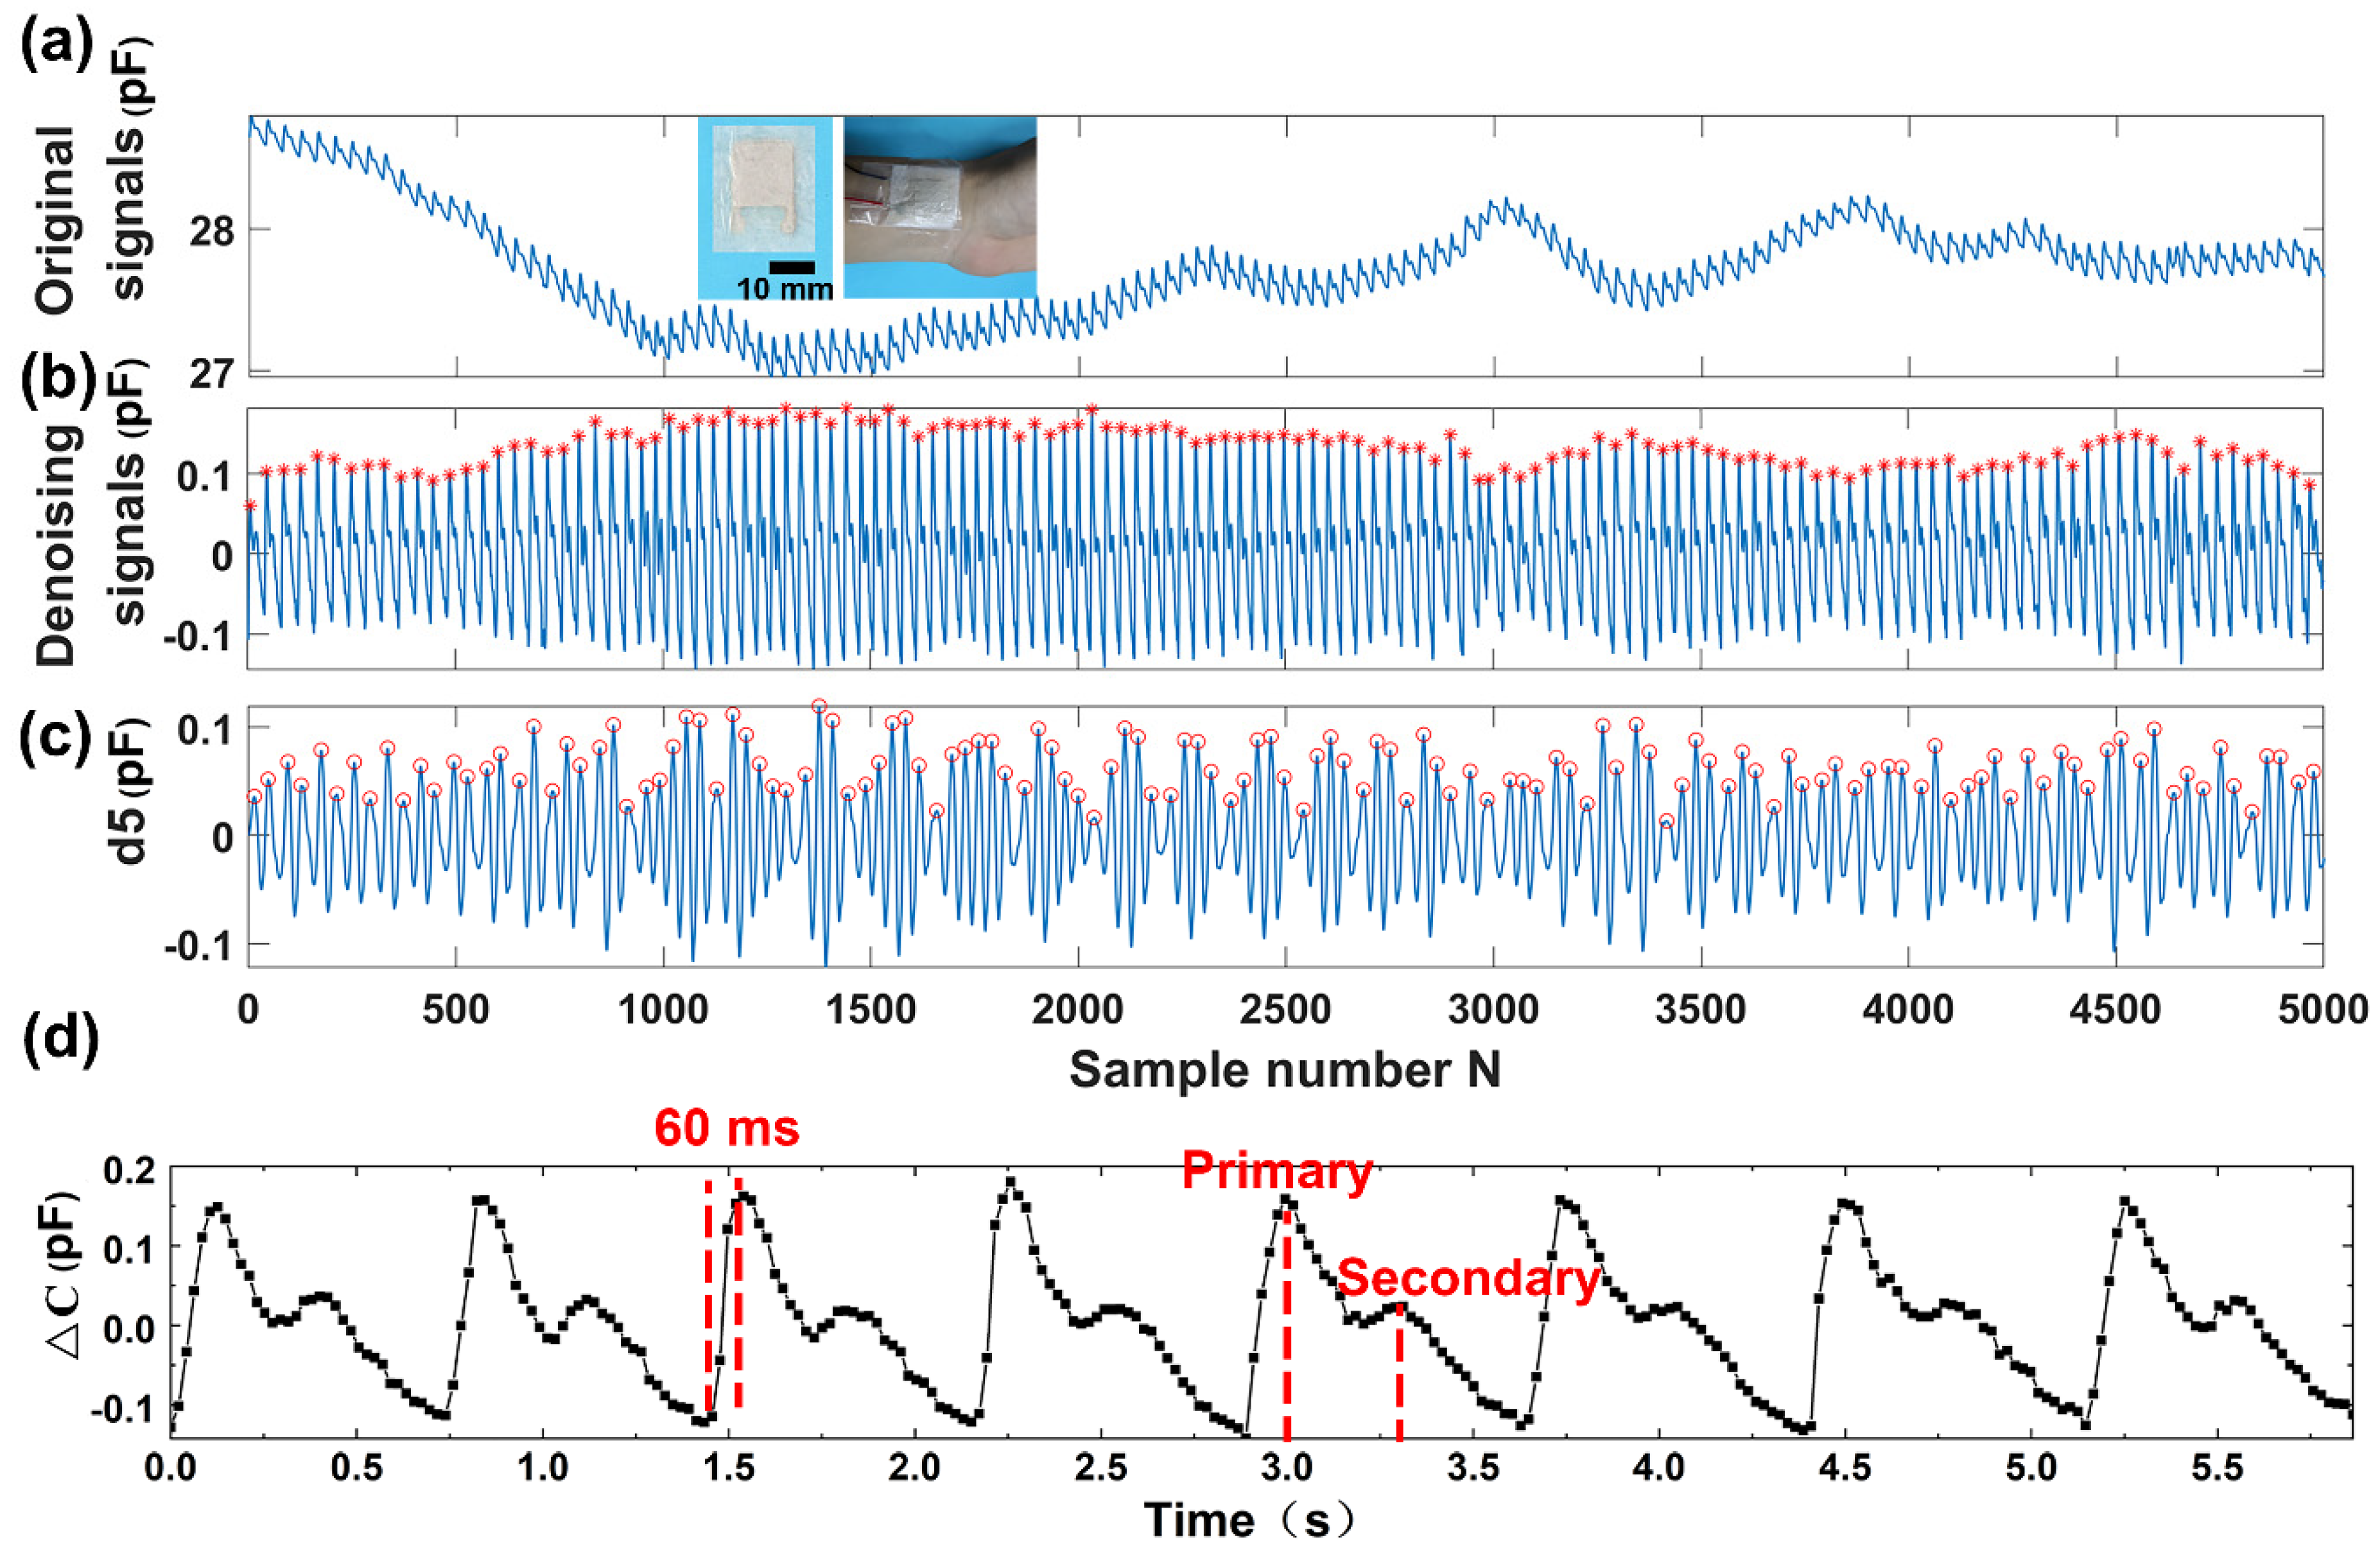

3.4. Detection of Wrist Pulse